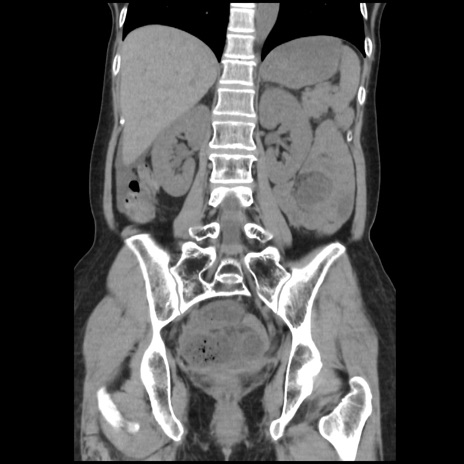

症例32(冠状断像)

【症例】40歳代 女性

【主訴】上腹部痛、嘔気・嘔吐

【現病歴】約9時間前頃から急に上腹部痛、嘔気、嘔吐が出現。改善しないため救急要請。

【既往歴】子宮頚癌(広汎子宮全摘術、放射線療法)、腸閉塞

【身体所見】腹部:平坦、軟、腸雑音亢進、上腹部を中心に腹部全体に圧痛あり。

【データ】WBC 8400、CRP 0.03